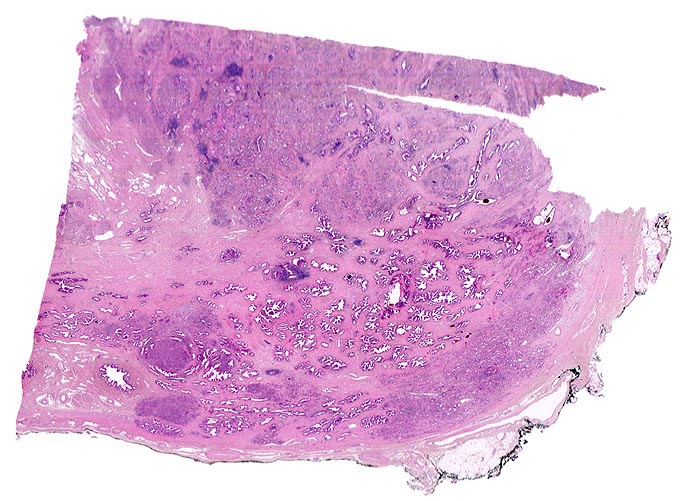

• Normale Prostatadrüsen mit grossen Lumina angeordnet in Läppchen. Das Epithel bildet Falten und besteht aus einer inneren hochprismatischen sekretorischen Zellschicht und einer äusseren Schicht flacher Myoepithelien.

• Herde kleiner Karzinomdrüsen ohne Basalzellschicht.

• Fehlende lobuläre Anordnung der Karzinomdrüsen.

• Links oben im Präparat finden sich Anteile der Samenblase mit polymorphem Epithel und gelben Lipofuszinpigmenteinlagerungen.

• Unterhalb der Samenblase sind von flachem Endothel ausgekleidete Lymphgefässe mit Karzinominfiltraten erkennbar (Lymphangiosis carcinomatosa).

• Der mit schwarzer Tusche markierte Resektionsrand in der unteren Hälfte des Präparates ist tumorfrei.